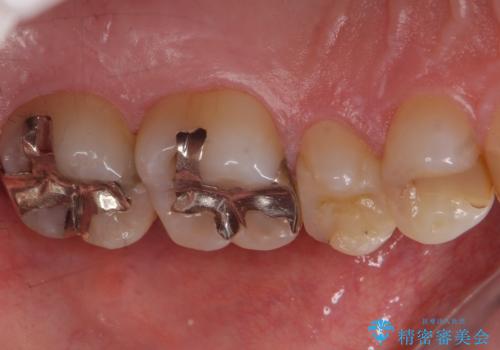

- 銀歯のやり替えをご希望で来院されました。

虫歯を取りつつ銀歯を外し、セラミックインレーでの修復処置を行います。

処置中に手前の歯の詰め物の不適合が確認されたため、追加で治療していくこととなりました。